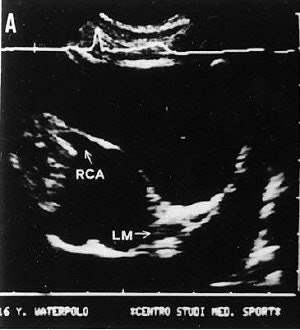

| Seventeen-year-old asymptomatic basketball player. Rest ECG was normal except for rare ventricular escape beats, singled and coupled. Two-dimensional transesophageal echocardiography (TEE) of the left parasternal short-axis aortic view. Panel B (below) clearly shows the right coronary artery (RCA) originating abnormally from the left sinus of the Valsalva, close to the left coronary ostium and the left main (LM), and running around between the aorta and pulmonary artery; for comparison, panel A (above) shows the normal position of coronary ostia in a 16-year-old water polo player. |

![]() |